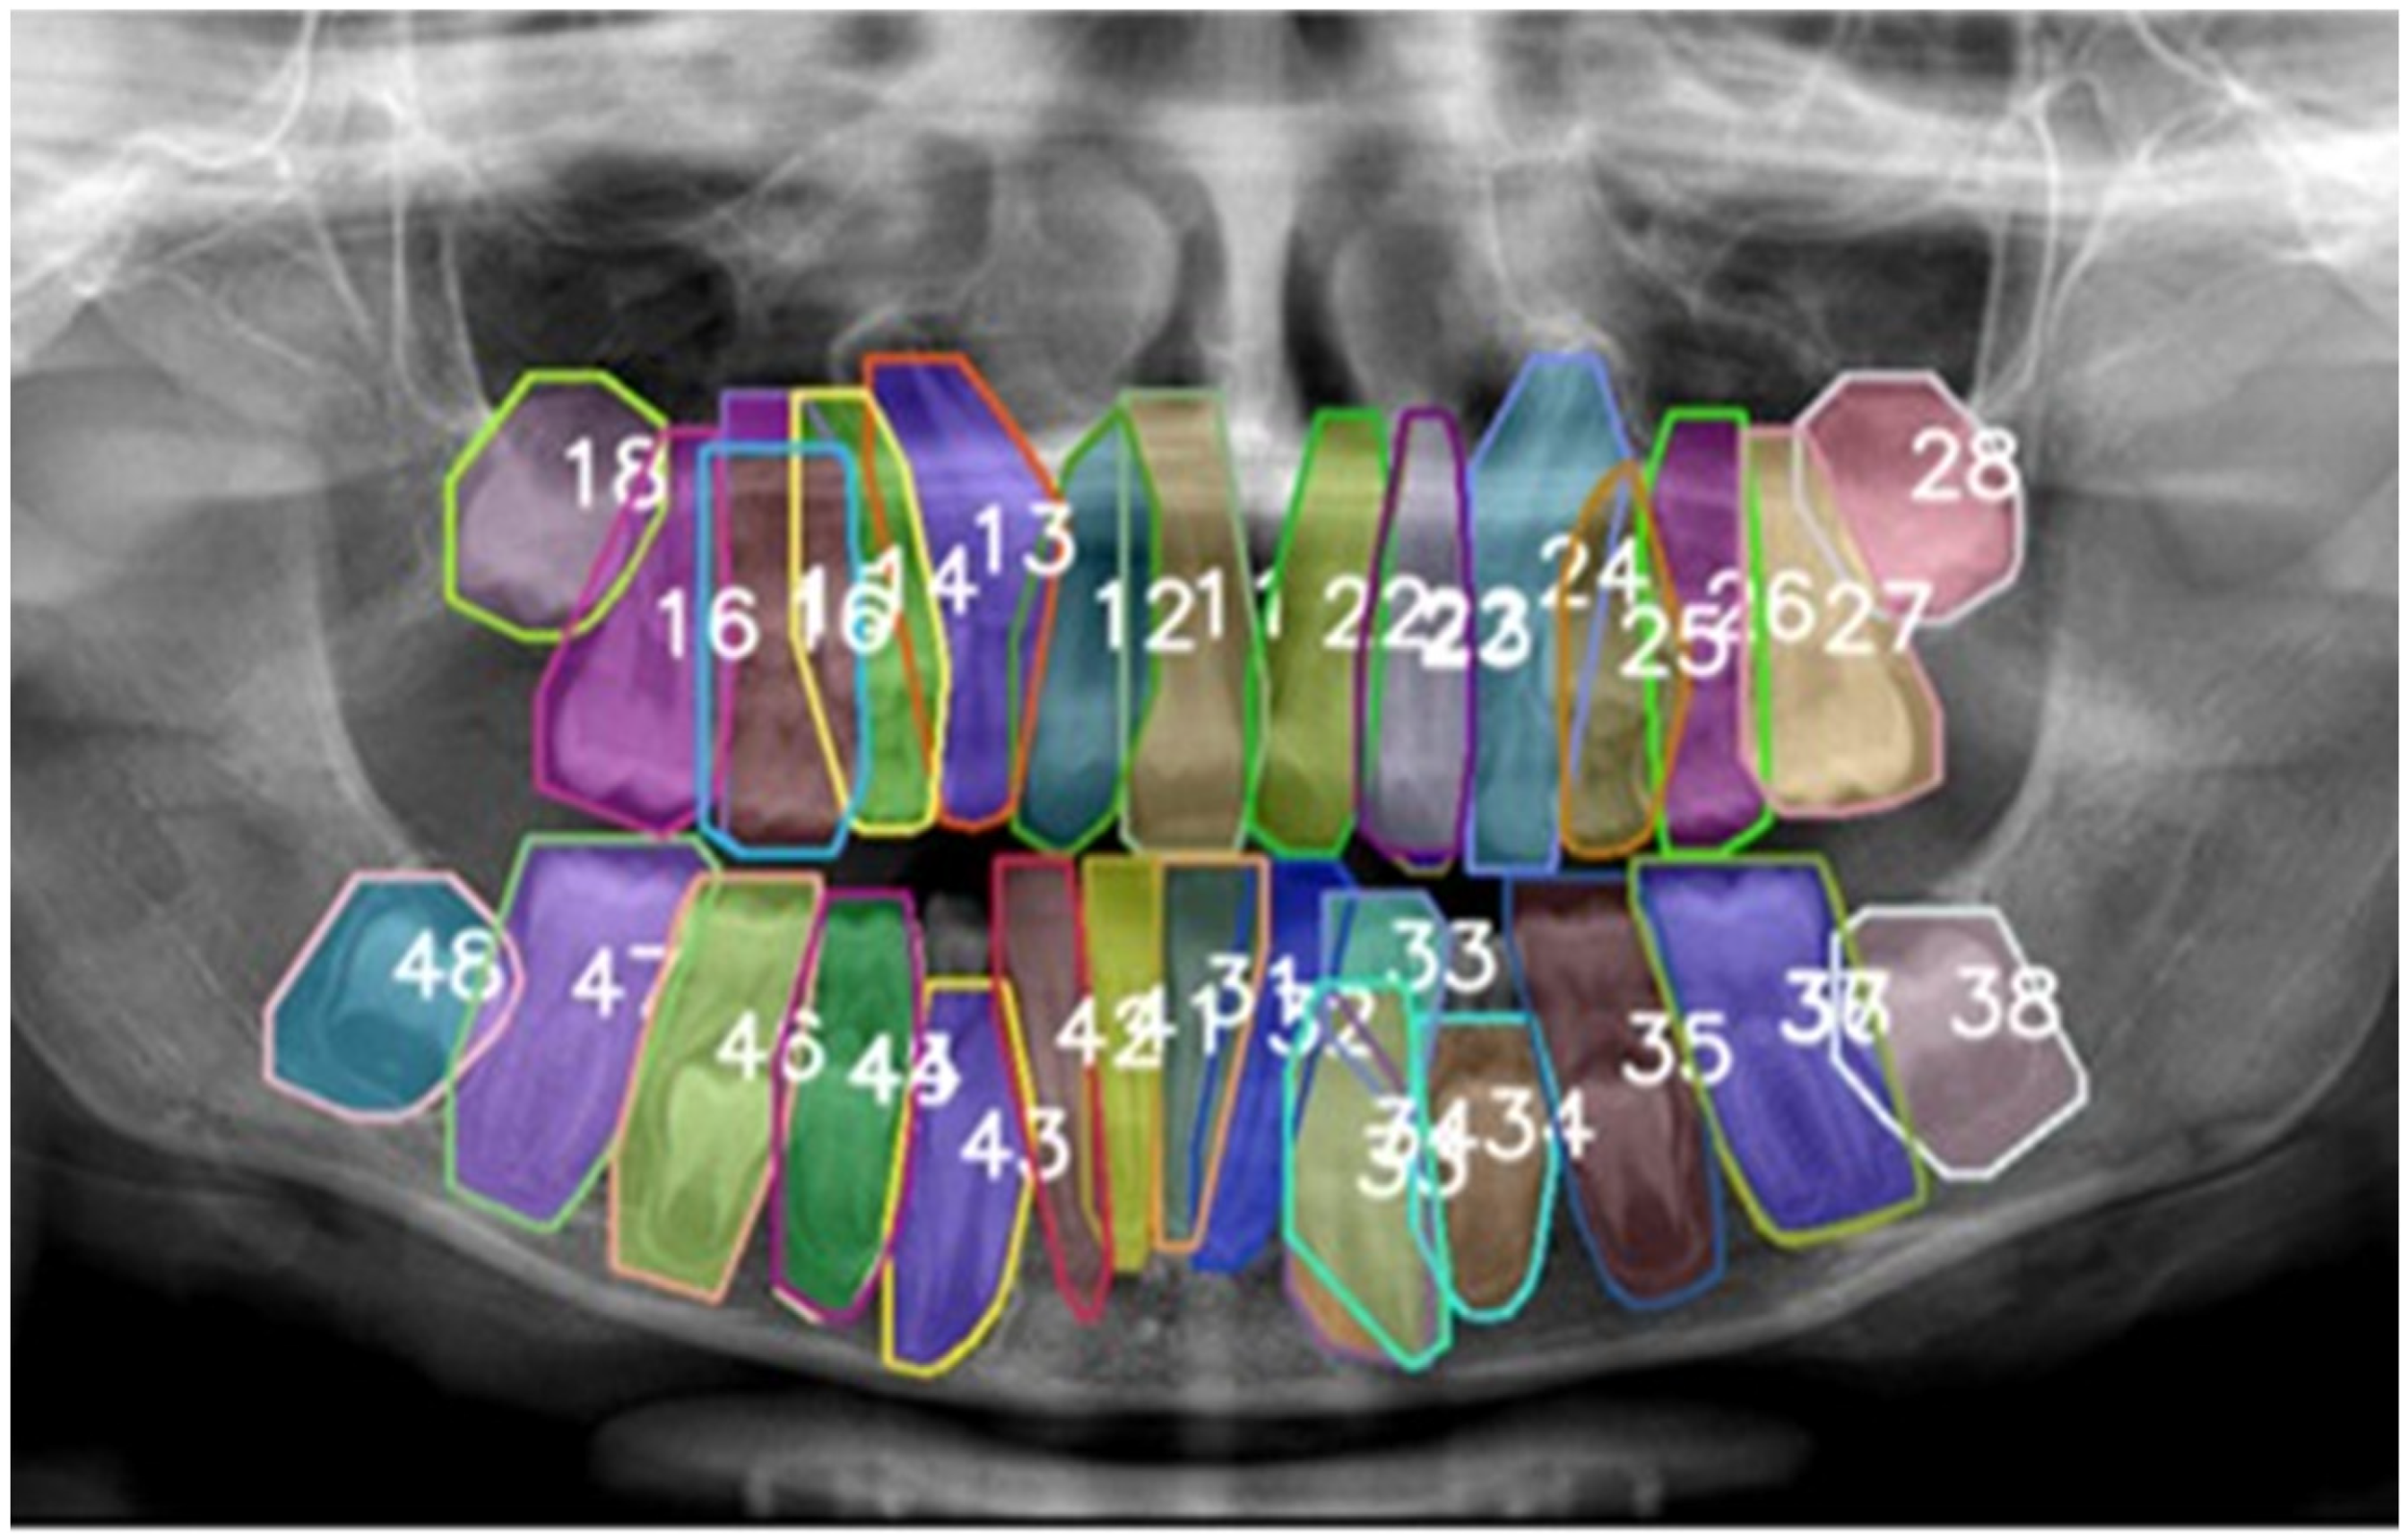

- detect the location of each object (in our case, each tooth),

- classify the object (e.g., tooth 11, tooth 12, tooth 35, etc.), and

- segment its precise contour (tooth boundary).

- bounding box coordinates (x, y, width, height),

- class label (e.g., 11, 12, …), and

- an instance-specific segmentation mask.